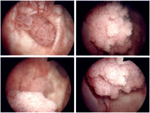

Ουάσιγκτον: Αμερικανοί επιστήμονες ανακάλυψαν αρχέγονα καρκινικά κύτταρα της ουροδόχου κύστης που μεταμφιέζονται με ένα σήμα που τρομάζει τα κύτταρα του ανοσοποιητικού συστήματος, επιτρέποντάς τους έτσι να ωριμάσουν και να εξελιχθούν τελικά σε όγκο.